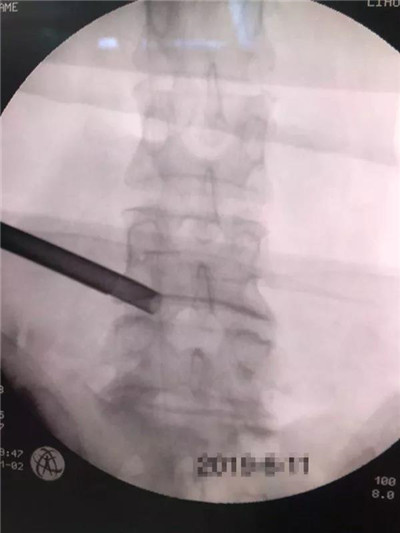

骨三科主任刘利群一直重视骨科微创技术的发展,主张用微创的手术方式为患者解除病患。为了改变腰间盘突出症手术传统术式的弊端,切实提高患者的愈后疗效,鼓励青年医生卢海波学习开展微创椎间孔镜下椎间盘摘除术。卢海波曾到北京朝阳医院脊柱外科学习一年,并多次参加培训、讲座,研读文献,向有经验的教授专家学习、请教,多次观摩、演练,做好充足准备,6月11日,历经2个小时,终于成功摘除了“作怪”的突出间盘,患者两天后即恢复正常,腰腿疼痛完全缓解。

卢海波介绍,实施椎间孔镜下间盘摘除术,需患者在局麻状态下,经C臂机引导定位,穿刺,把椎间孔镜送到腰椎间盘突出的位置,再把髓核钳通过孔镜穿进去,去除病变的间盘。相比传统开刀手术,孔镜手术安全性更高,手术全程可视下操作,伤口只有6毫米左右,不易感染,不破坏肌肉附着点,不影响脊柱稳定性,术后2-3天就可以下床行走。